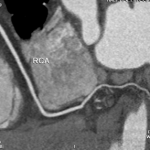

女性,43歲,心跳速率每分鐘56下,BMI: 20 顯影劑速率4.0ml/s 總量 67ml/輻射劑量1.9mSv